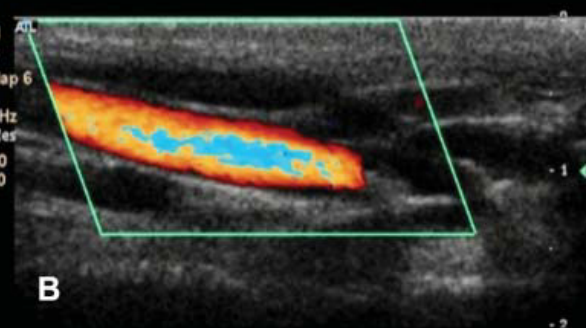

Name this artifact.

What is the cause of the artifact? How would you (try to) fix it?

Aliasing artifact: occurs when the doppler shift frequency exceeds the Nyquist limit (1/2 PRF) –> information is mapped to the wrong side of baseline.

FIX: increase PRF, move baseline, decrease frequency, increase Doppler angle